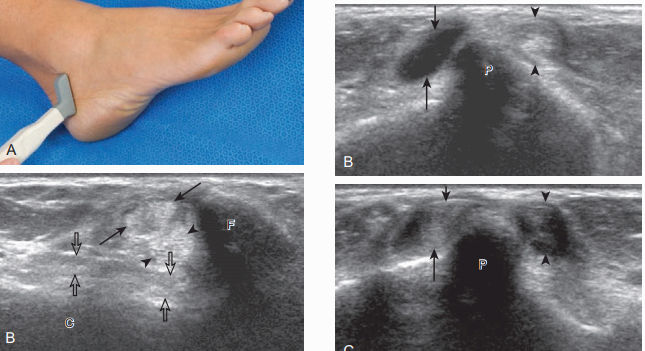

발꿈치종아리인대를 보기 위해서는 종아리뼈끝과 발꿈치뼈의 뒤 사이에 탐촉자를 세로방향으로 놓는다. 이 인대는 종아리근힘줄보다 깊은 곳에서 종아리뼈와 발꿈치뼈의 뒤-가쪽사이를 연결한다. 비등방성 때문에 정상적인 발꿈치종아리인대가 낮은 에코로 보여서 종아리근힘줄과 관계된 신경 절낭(ganglion cyst)으로 오인할 수 있다.